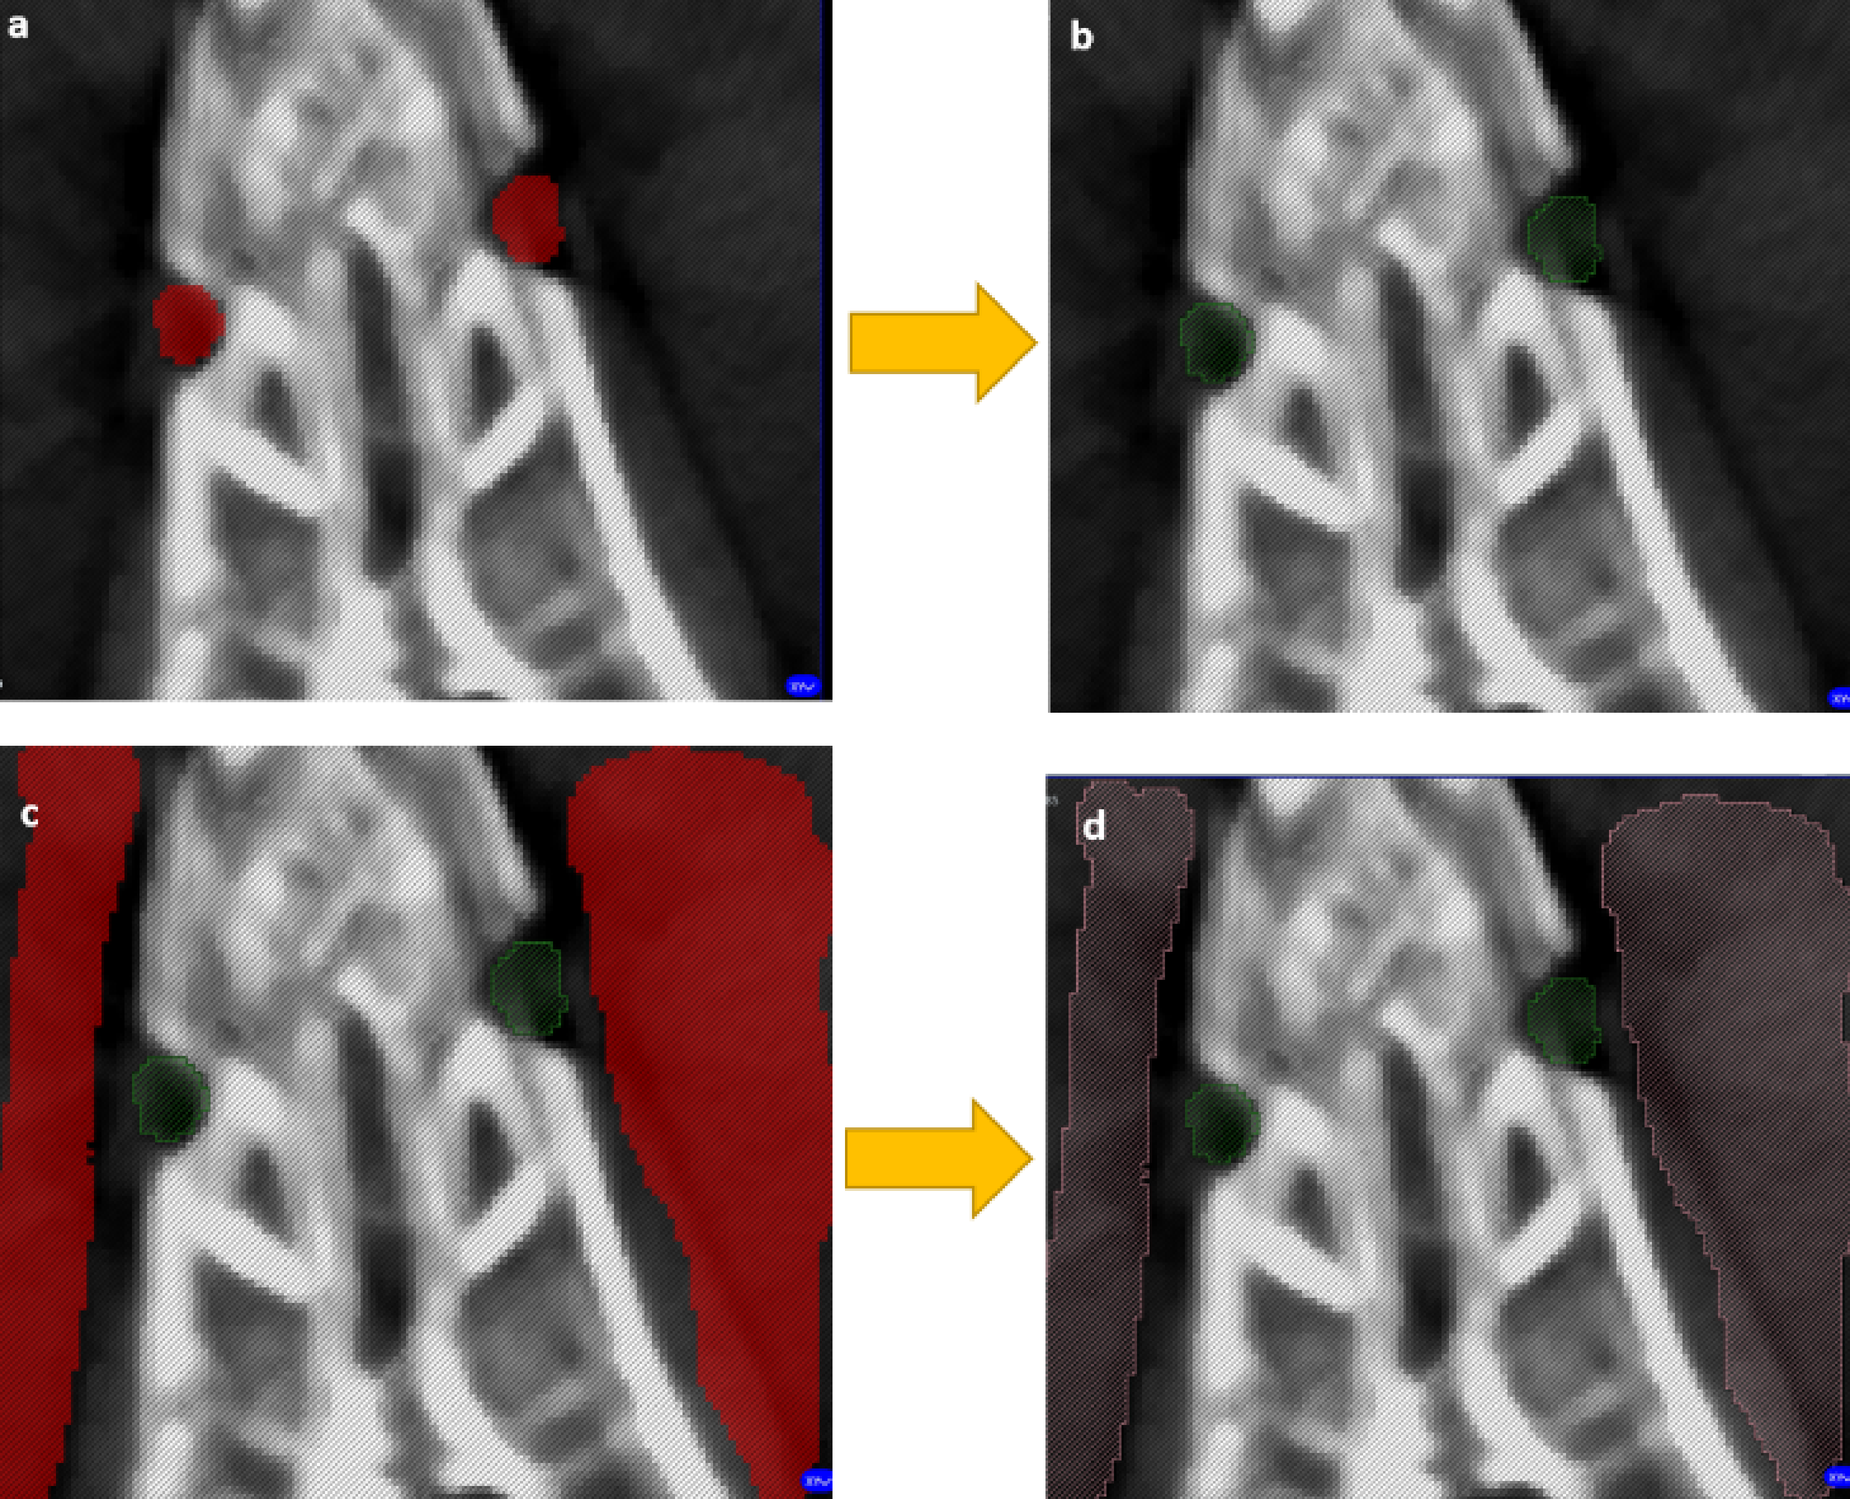

Training process for the ResNet18-encoded U-Net model in Avizo. Examples of training slices show the model learning to segment the defect (a, b) and background (c, d) classes.